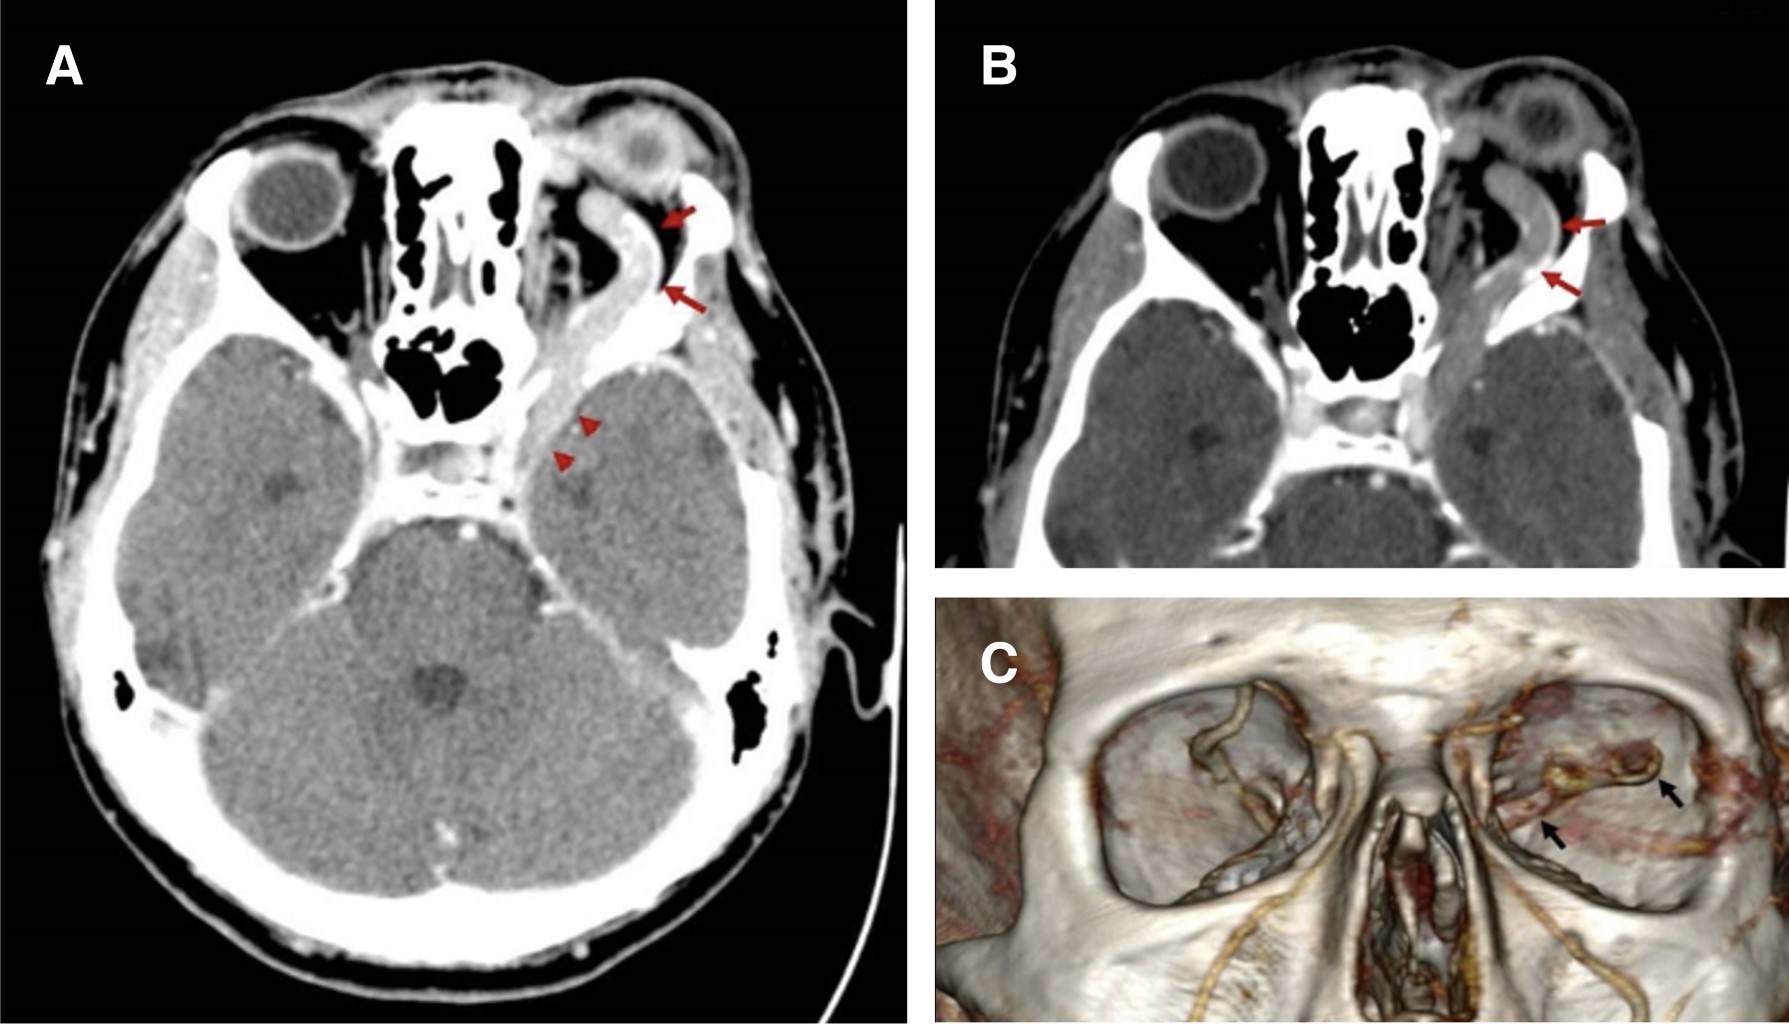

Una tomografía computarizada multifásica reveló exoftalmia izquierda con dilatación y trombosis parcial de la vena oftálmica izquierda aparentemente secundaria a trombosis del seno cavernoso ipsilateral (Figura 1) y un hallazgo incidental de un signo de cabeza de medusa en el ángulo del cuerno anterior del ventrículo derecho con la presencia de una vena dural colectora (Figura 2). En este momento, se sospechó de una fístula arteriovenosa dural del seno cavernoso, secundaria a los antecedentes traumático-quirúrgicos.

Figura 1

Figura 2